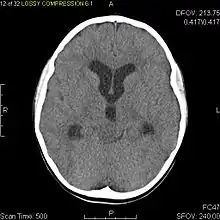

Usually – depending on the interview of the patient and after a clinical exam which includes a neurological exam and an ophthalmological exam – a CT scan and/or an MRI scan will be performed to confirm the presence of a tumor. They are usually easily distinguishable from normal brain structures using these imaging techniques. A special dye may be injected into a vein before these scans to provide contrast and make tumors easier to identify. Pilocytic astrocytomas are typically clearly visible on such scans, but it is often difficult to say based on imaging alone what type of tumor is present.

| Diagnostic method | MRI, CT scan |